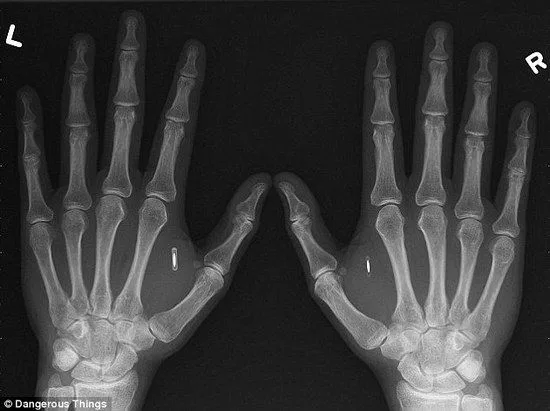

ความสะดวกของ RFID ที่ทำงานไวกว่าระบบอ่านลายนิ้วมือมาก บริษัท NewFusion ในประเทศเบลเยียมได้เริ่มแนะนำให้พนักงงานฝังชิปที่มีขนาดเท่าเมล็ดข้าวนี้ไว้ที่ง่ามนิ้วระหว่างนิ้วหัวแม่มือกับนิ้วชี้

ชิปที่ฝังในมือพนักงานนี้จะใช้สำหรับระบุตัวตนตั้งแต่การลงเวลาเข้างาน การล็อกอินเข้าระบบคอมฯโดยไม่ต้องพิมพ์พาสเวิร์ด การใช้เครื่องถ่ายเอกสารโดยไม่ต้องพิมพ์พาสเวิร์ด เปิดประตูเข้าไปในโซนต่างๆของบริษัท และอนาคตอาจมีการพัฒนาไปเป็นสัญญาณกุญแจรถคือเดินขึ้นรถบริษัทไปกดปุ่มสตาร์ทเลย โดยชิปนี้เริ่มมีการใช้งานมาตั้งแต่ปี 2015 ในบริษัทรักษาความปลอดภัยแห่งหนึงในประเทศสวีเดน ซึ่งพนักงานที่ฝังชิปในบริษัทนั้นนอกจากเอาไว้เปิดประตูห้องลับต่างๆยังเอามูลค่าเงินที่เติมในชิปไว้จ่ายค่าอาหารกลางวันในโรงอาหารของบริษัทด้วย